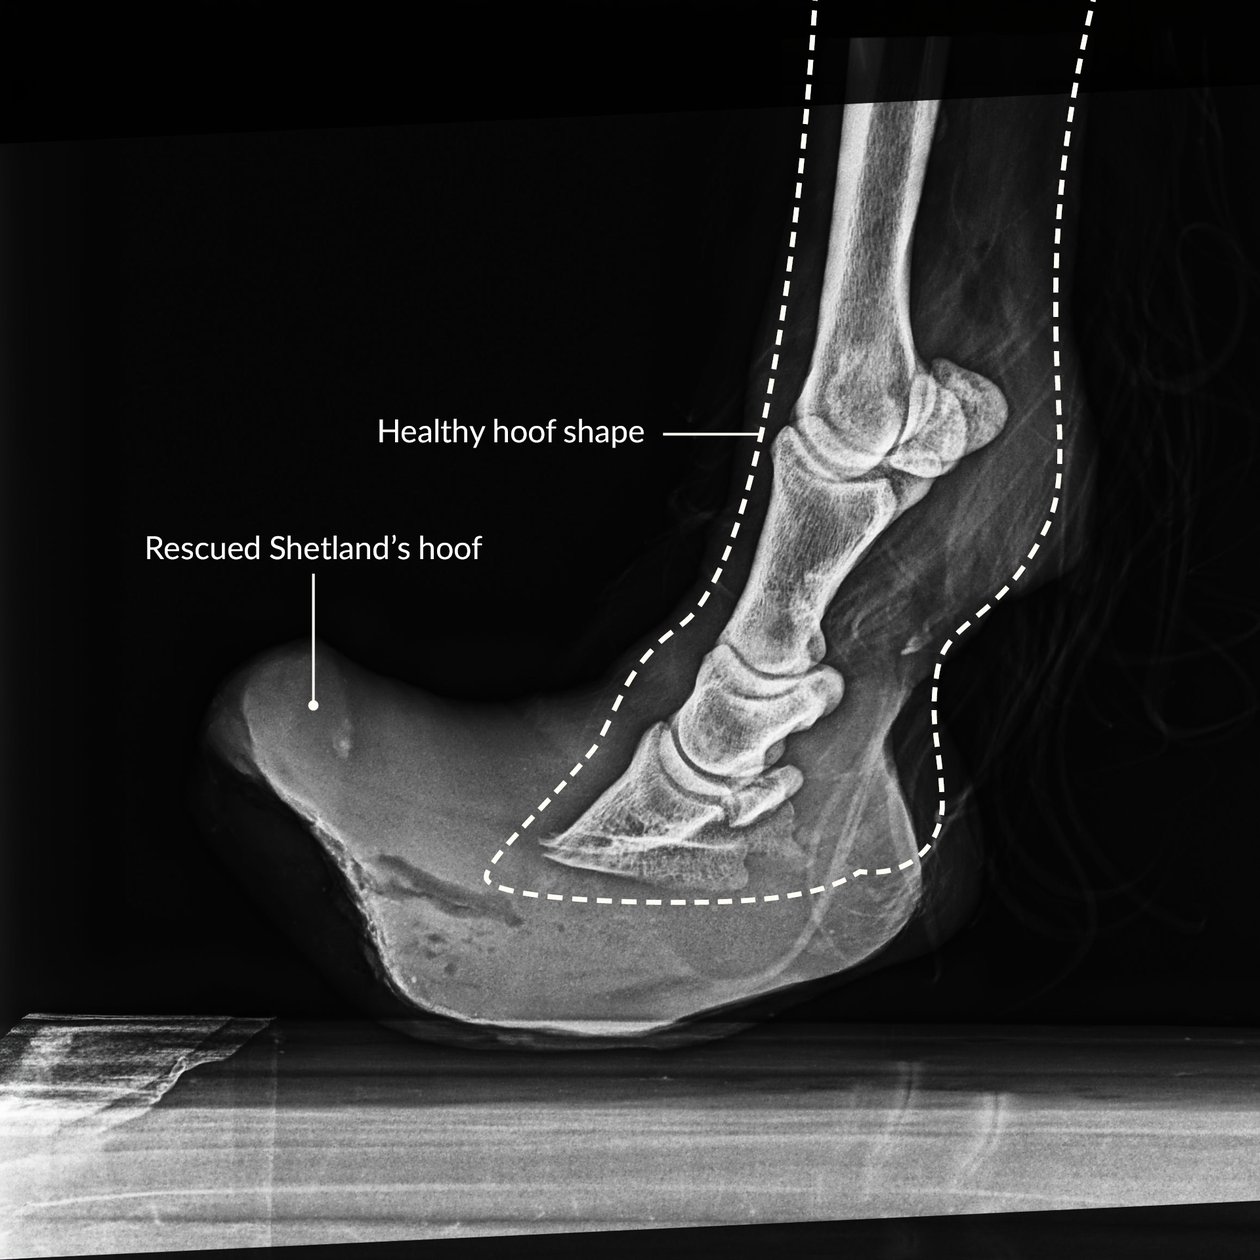

When HorseWorld’s welfare team first met the ponies, they found extreme hoof overgrowth that had been left untreated for so long it caused painful changes to the structure of their feet. Once safely in the charity’s care, vets confirmed their condition was the result of prolonged neglect over time. Despite everything they had been through, the ponies showed incredible spirit.

HorseWorld quickly stepped in to provide the specialist care they urgently needed. They are now receiving ongoing veterinary treatment, corrective farriery, tailored nutrition and careful pain management. Their recovery won’t be quick or easy, and is likely to take many months, putting a significant strain on the charity’s resources. The situation is made even more challenging by an active legal case connected to their rescue. Because of this, HorseWorld cannot currently share the ponies’ identities or show full-body images, which makes fundraising more difficult.